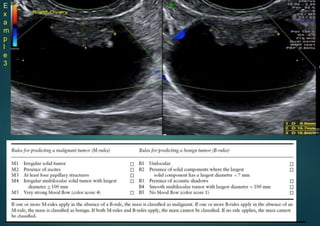

Simple Rules

FEATURES of a benign mass (B-features)

A mass is classified as

benign if at least one B-

feature is present and no

M-features are present

FEATURES of a malignant mass (M features)

malignant if at least one

M-feature is present and

no B-features are present

Rule 1: If one or more M features are present in

absence of B feature(s), the mass is classified as

malignant.

• Rule 2: If one or more B features are present in

absence of M feature(s), the mass is classified as

benign.

• Rule 3: If both M features and B features are present,

or if no B or M features are present, the result is

inconclusive and a second stage test is recommended.

E

x

a

m

p

l

3

• IOTA descrition – Unilocular, unilocular-solid, multilocular, multilocular-solid or solid

–

Cyst contents – anechoic, low level, ground glass, hemorrhagic or mixed –

Uncertain (NO BENIGN RULES AND NO MALIGNANT RULES = UNCERTAIN

Example 3

Simple rules:UNCERTAIN

Borderline ovariantumour